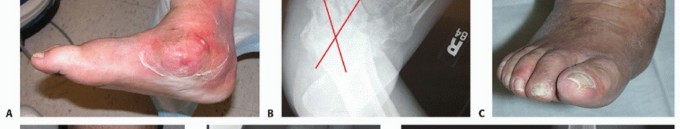

When followed longitudinally, patients who are clinically nonplantigrade, that is, have a noncolinear lateral talarfirst metatarsal axis, as determined from weight-bearing dorsal-plantar radiographs, are likely to develop

foot ulcers overlying the deformity over time.2,16 These patients are best treated with surgical correction of their acquired deformity(FIG 4).

FIG 4 • A. This 58-year-old, morbidly obese diabetic accountant is clinically bearing weight on the medial skin overlying the uncovered talar head. B. The talar-first metatarsal axis is noncolinear. Patients who are both radiographically and clinically nonplantigrade are likely to develop skin breakdown through nonplantar skin overlying bony deformity. C,D. The patient was successfully treated with surgical correction of the deformity and longitudinal management with therapeutic footwear. E,F. Clinical photographs and weight-bearing radiographs 2 years following surgery.

This extremely cooperative patient demonstrates the difficulties in longitudinal management of the nonplantigrade patient without correction of the deformity. The acute destructive process was successfully treated with a total contact cast. The patient carefully followed instructions, wearing the therapeutic footwear full time and returning for scheduled visits to both the physician and pedorthist. Despite close monitoring, the patient developed an ulcer in the skin overlying the head of the talus. When multiple surgical attempts failed, a transtibial amputation was necessary because of infection (FIG 5).